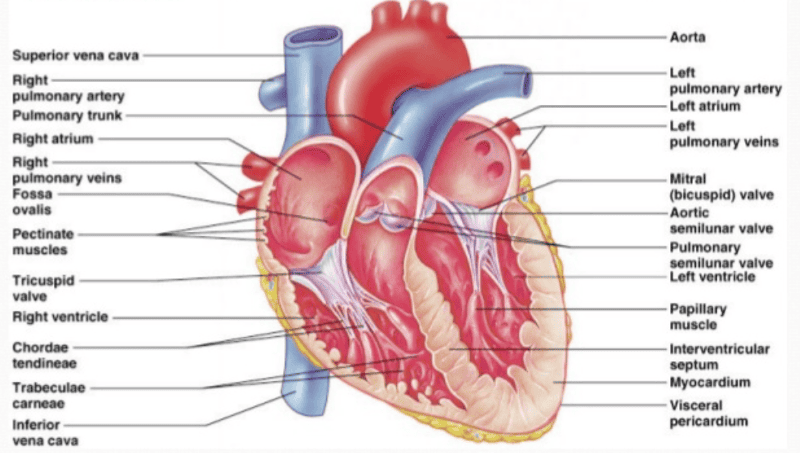

Gross Anatomy of the Heart

[Definiton of] Blood pressure

The pressure of blood in the circulatory system

[Definiton of] Systolic Pressure

The pressure in blood vessels when the heart contracts

[Definiton of] Diastolic Pressure

The pressure in blood vessels when the heart is at rest (between beats)

Units used to measure blood pressure

mmHg (millimeters of mercury)

[Definiton of] Heart Murmur

A swishing sound (in addition to the normal lub/dub) when there is abnormal blood flow across heart valves

[Definiton of] Sounds of Korotkoff

Characteristic sounds of resumption of blood flow to forearm when using a sphygmomanometer

[Definiton of] Pulse Pressure

The difference between systolic and diastolic pressure (PP= S - D)

What is the longest vein?

The great saphenous vein

Left ventricle and atrium

Right ventricle and atrium

Artery

Vein